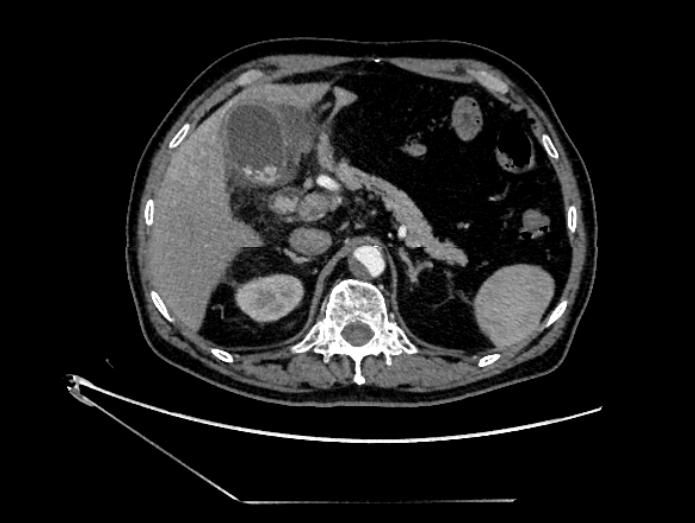

突如其来的腹痛、发热、寒战、黄疸近日,年龄高达78岁的潘大爷讲述自己前些天毫无征兆突发腹部胀痛,伴有发烧、寒颤、恶心呕吐、胸闷、小便黄,实在忍...

“谈癌色变”,恶性肿瘤尤其是消化系肿瘤已经成为严重威胁我国人群健康的主要公共卫生问题之一,恶性肿瘤死亡占居民全部死因的23.91%,且近年来...